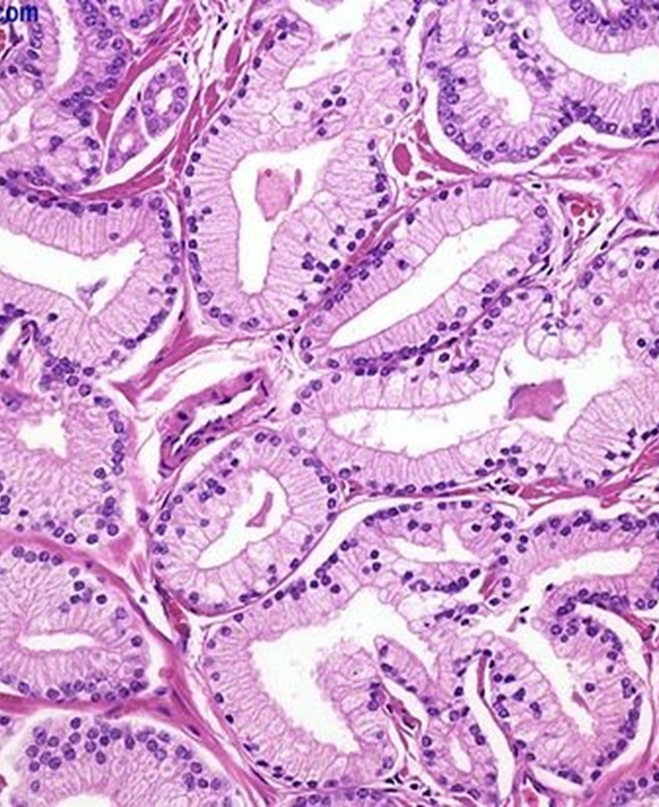

Pathology

Most common form is adenocarcinoma (glandular prostate cancer).

Lined by a single uniform layer of cuboidal or low columnar epithelium.

The outer basal cell layer typical of benign glands is absent.

Cancer glands are more crowded and characteristically lack branching and papillary infoldings.